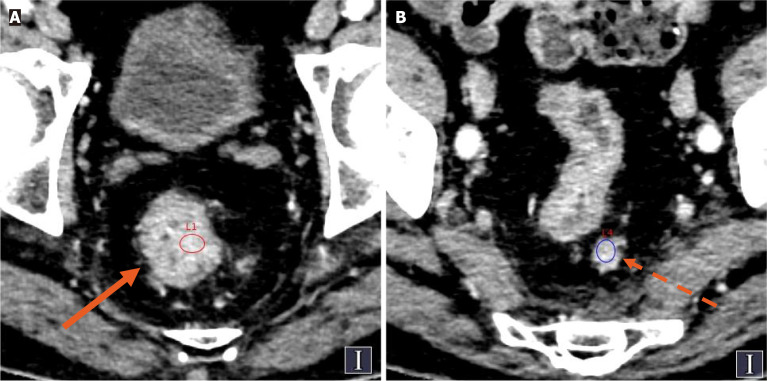

Methods: A retrospective analysis was conducted which included 121 patients with CRC whose complete spectral CT data were available. Patients were divided into the TDs+ group and the TDs- group on the basis of their pathological results. Spectral CT parameters of the primary CRC lesion and the largest regional LNs were measured, including the normalized iodine concentration (NIC) in both the arterial and venous phases, and the LN-to-primary tumor ratio was calculated. Statistical methods were used to evaluate the diagnostic efficacy of each spectral parameter.

Results: Among the 121 CRC patients, 33 (27.2%) were confirmed to be TDs+. The risk of TDs positivity was greater in patients with positive LN metastasis, higher N stage and elevated carcinoembryonic antigen and cancer antigen 19-9 levels. The NIC (LNs in both the arterial and venous phases), NIC (primary tumors in the venous phase), and the LN-to-primary tumor ratio in both the arterial and venous phases were associated with TDs (P < 0.05). In multivariate logistic regression analysis, the arterial phase LN-to-primary tumor ratio was identified as an independent predictor of TDs, demonstrating the highest diagnostic performance (area under the curve: 0.812, sensitivity: 0.879, specificity: 0.648, cutoff value: 1.145).